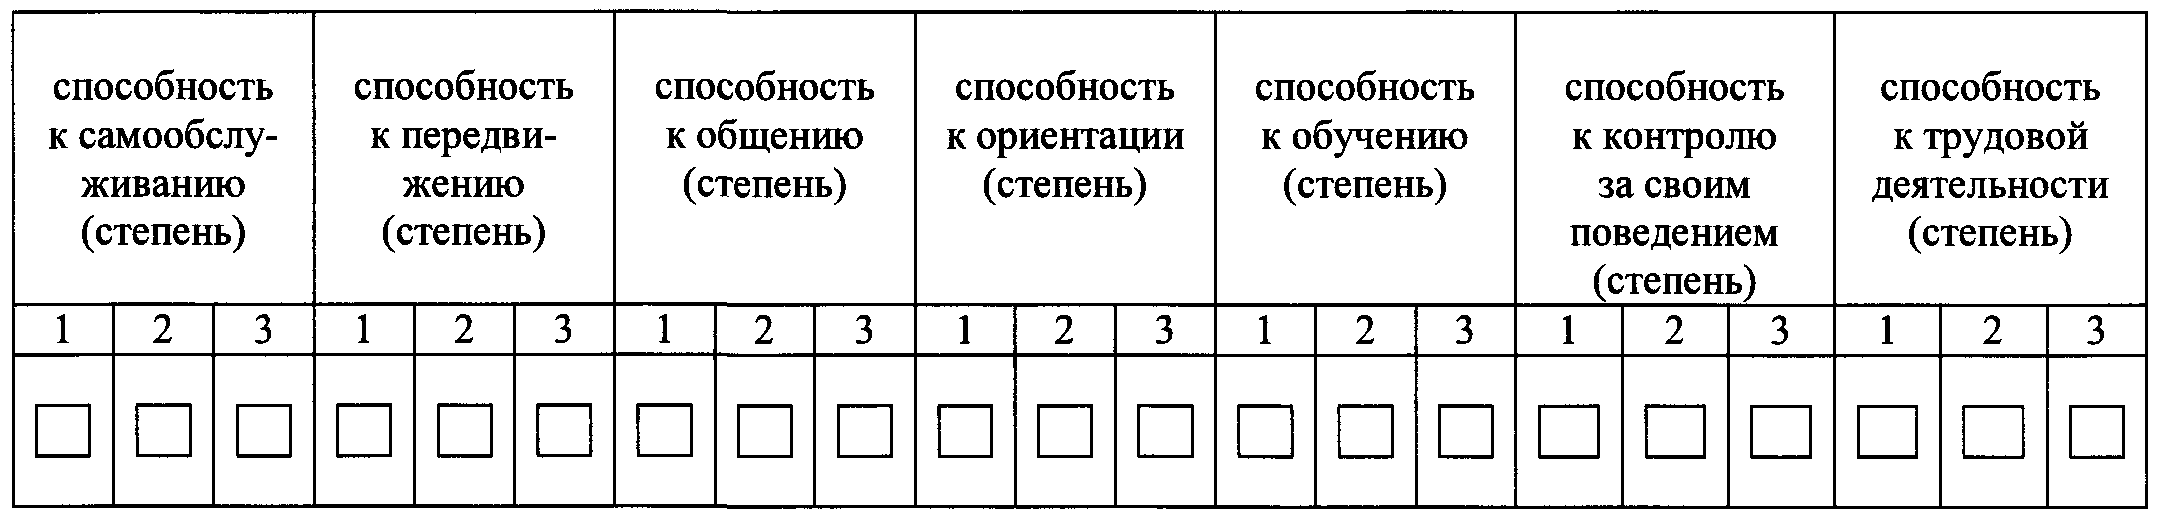

6. Ограничения основных категорий жизнедеятельности человека и степень их выраженности: